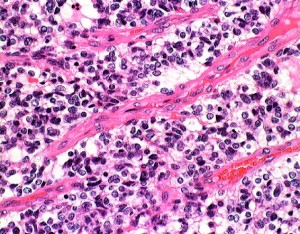

HE染色では細胞核の周りが抜けるような典型的なhalo(左側の写真)があります。1p/19q欠失があり,MIB染色率(右側)は4%でした。

一部で,細胞密度が高く,核の腫大とクロマチンの増量,核間距離の短縮があり,核分裂像が認められ,MIB-1染色率が10%です。組織学的には退形成性乏突起膠腫グレード3とされました。

IDH変異あり,1P/19q欠失あり,ATRX変異なしです。

同じ患者さんからの2カ所の病理標本です。左は乏突起膠腫グレード2と診断できますし,右は退形成性星細胞腫グレード3と診断できます。光顕診断では,両方合わせて,退形成性乏突起星細胞腫グレード3となります。ちなみに,olig2 強陽性,MIB-1 9%,1p/19q codeletionがありました。遺伝子診断を加えると退形成性乏突起膠腫となります。乏突起膠細胞系腫瘍では,術中迅速病理診断や定位脳生検術での診断は誤診を招くことが多くて危険です。

この部分のみを一見するとanaplastic astrocytomaです。しかし,他の大部分がoligoastrocytomaであり,かつての組織診断ではanaplastic oligoastrocytoma AOA WHO grade IIIです。

左側の病理像はanaplastic oligodendroglioma AO あるいはoligodendroglioma ODです。しかし,右の画像の様にpseudopallisading (necrosis)を示す部分があり,WHO grade 4と診断したくなるのですが,oligodendrglioma grade 3 ではnecrosisが混在してもgrade 3としてよいのです。